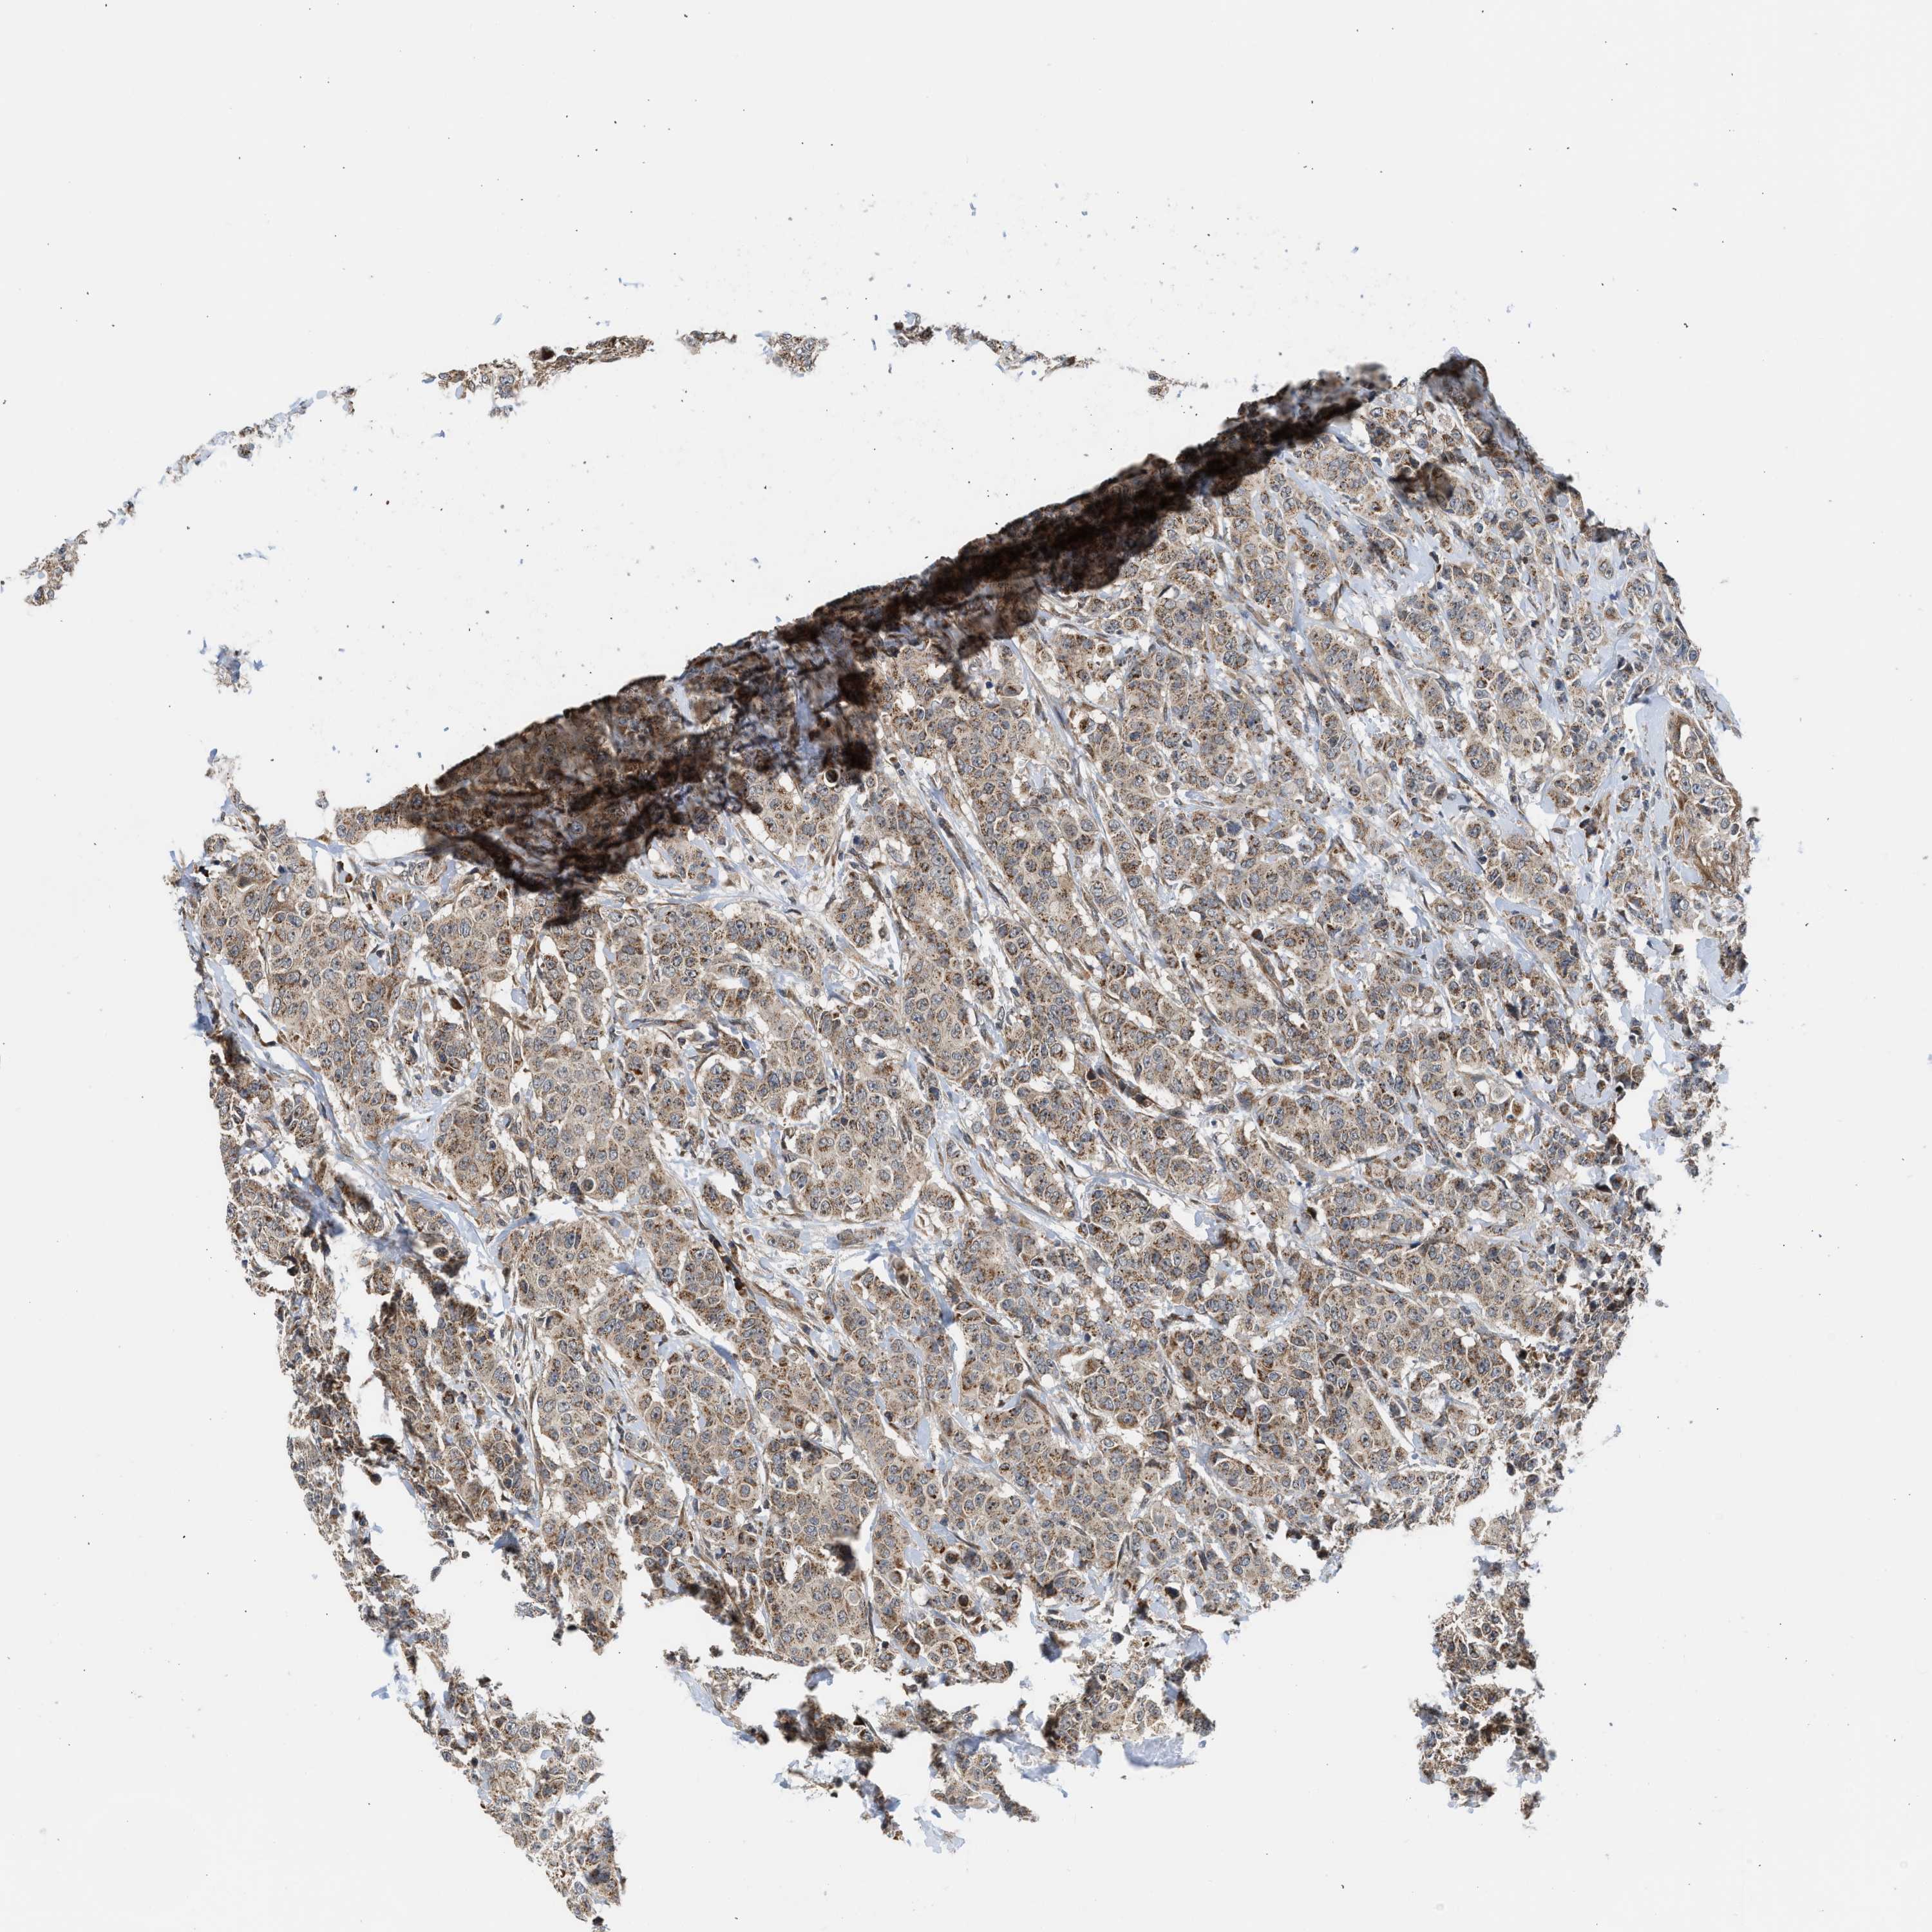

CANCER BREAST CANCER Show tissue menu

BRCA TCGA BRCA VALIDATION PROTEIN EXPRESSION

ANTIBODIES

AND

VALIDATION